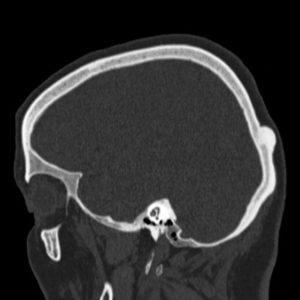

Остеома определяется на основе рентгеновского снимка затронутых костей. Для более глубокого анализа врач может назначить компьютерную томографию, которая позволяет точно определить местоположение опухоли и ее характеристики.

На этом рентгеновском снимке четко демонстрируется расположение опухоли: